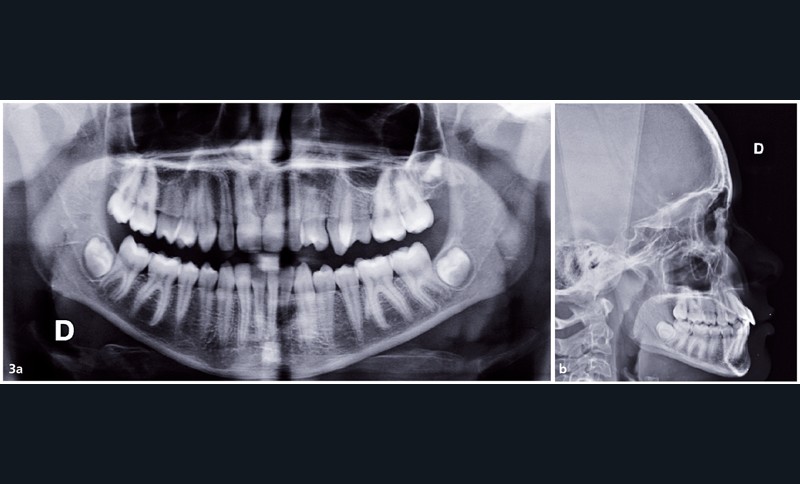

Au niveau squelettique, il présente une classe I tendance classe III (AoBo= -3,5mm) sur un schéma facial normodivergent.

Sur le plan occlusal et dentaire, on observe une classe III molaire et canine à gauche, une proalvéolie maxillaire, une occlusion inversée au niveau des 15/46 et 25/35-36, une non concordance des milieux incisifs et une transposition complète de 23 et 24 (fig. 2 et 3).